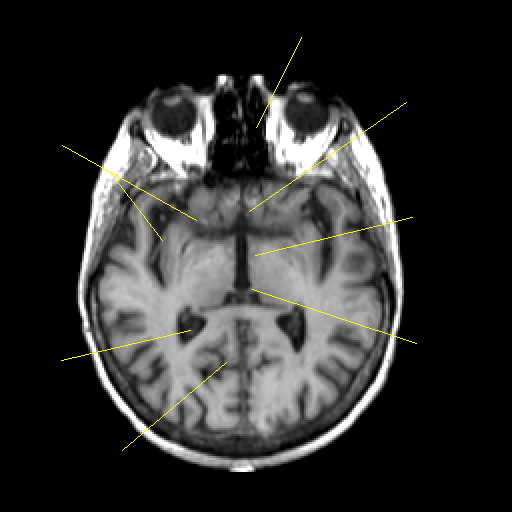

T1-weighted structural MR: Slice 25

Slice 25

Pointers

Labeled